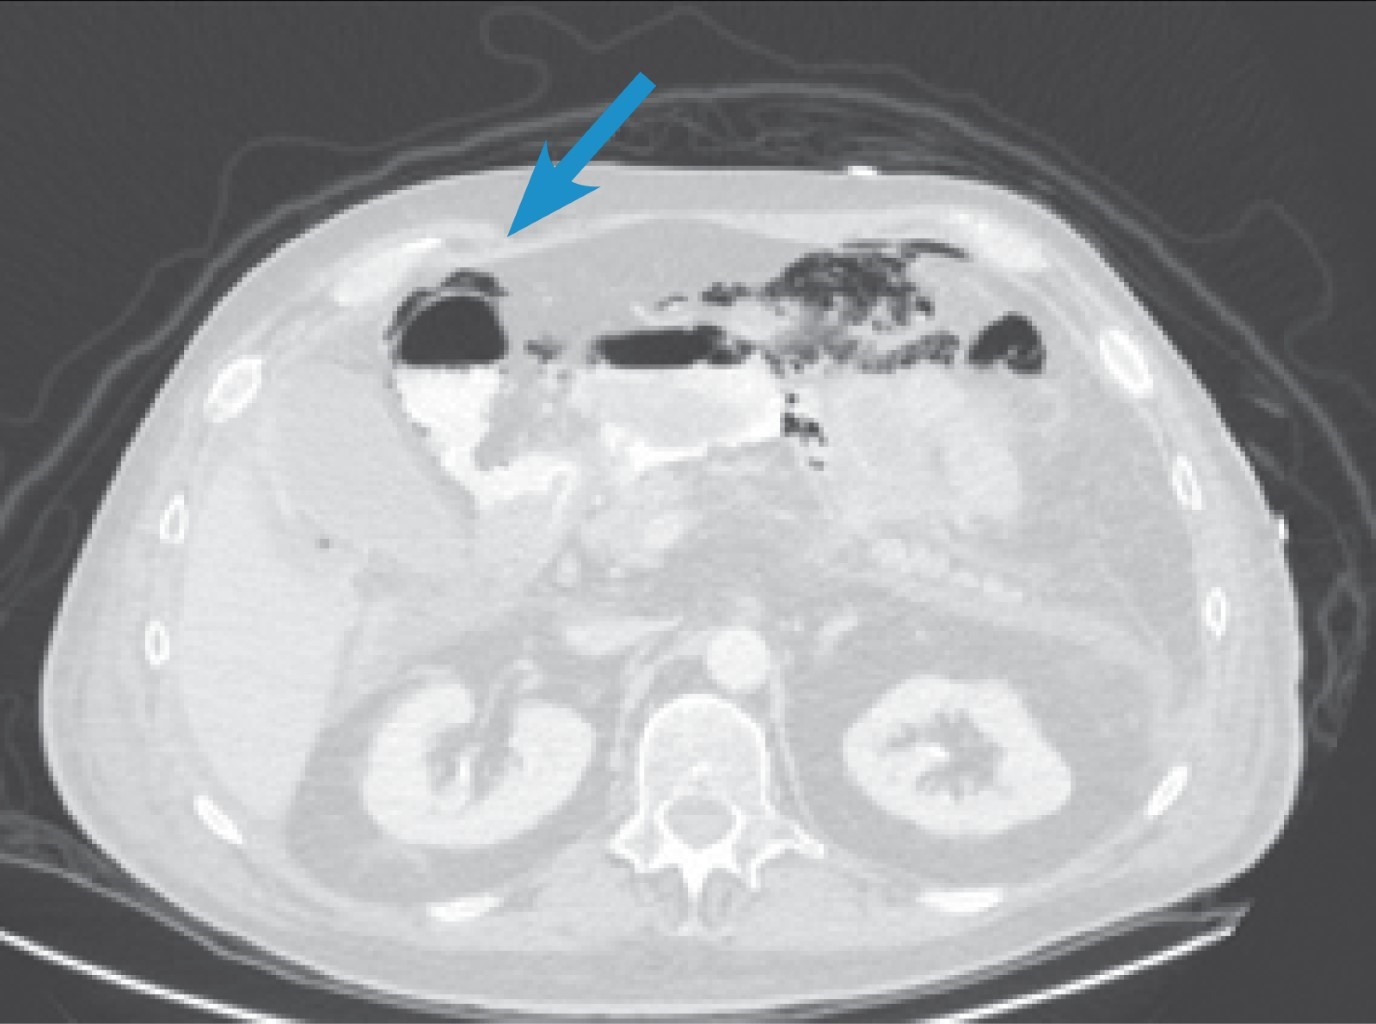

In the immediate postoperative period, the patient required management in the Intensive Care Unit due to hemodynamic instability with gradual improvement in the following days; invasive mechanical ventilation and aminergic support were removed on the third postoperative day. An esophagogastroduodenal series was performed on the fourth postoperative day, which was reported with the adequate passage of contrast medium into the jejunum without evidence of leakage (Figure 3). He started an oral diet without complications; the patient had a minimal serous output removed on the fifth postoperative day and a progressive decrease of duodenostomy output until discharge on postoperative day seven. He was discharged after his improvement. In ambulatory follow-up, duodenostomy was withdrawn on postoperative day 23.

Figure 3